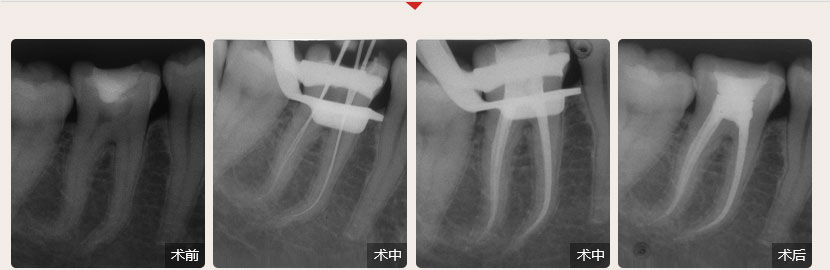

德倫口腔醫生全國根管治療技術競賽獲獎案例展示